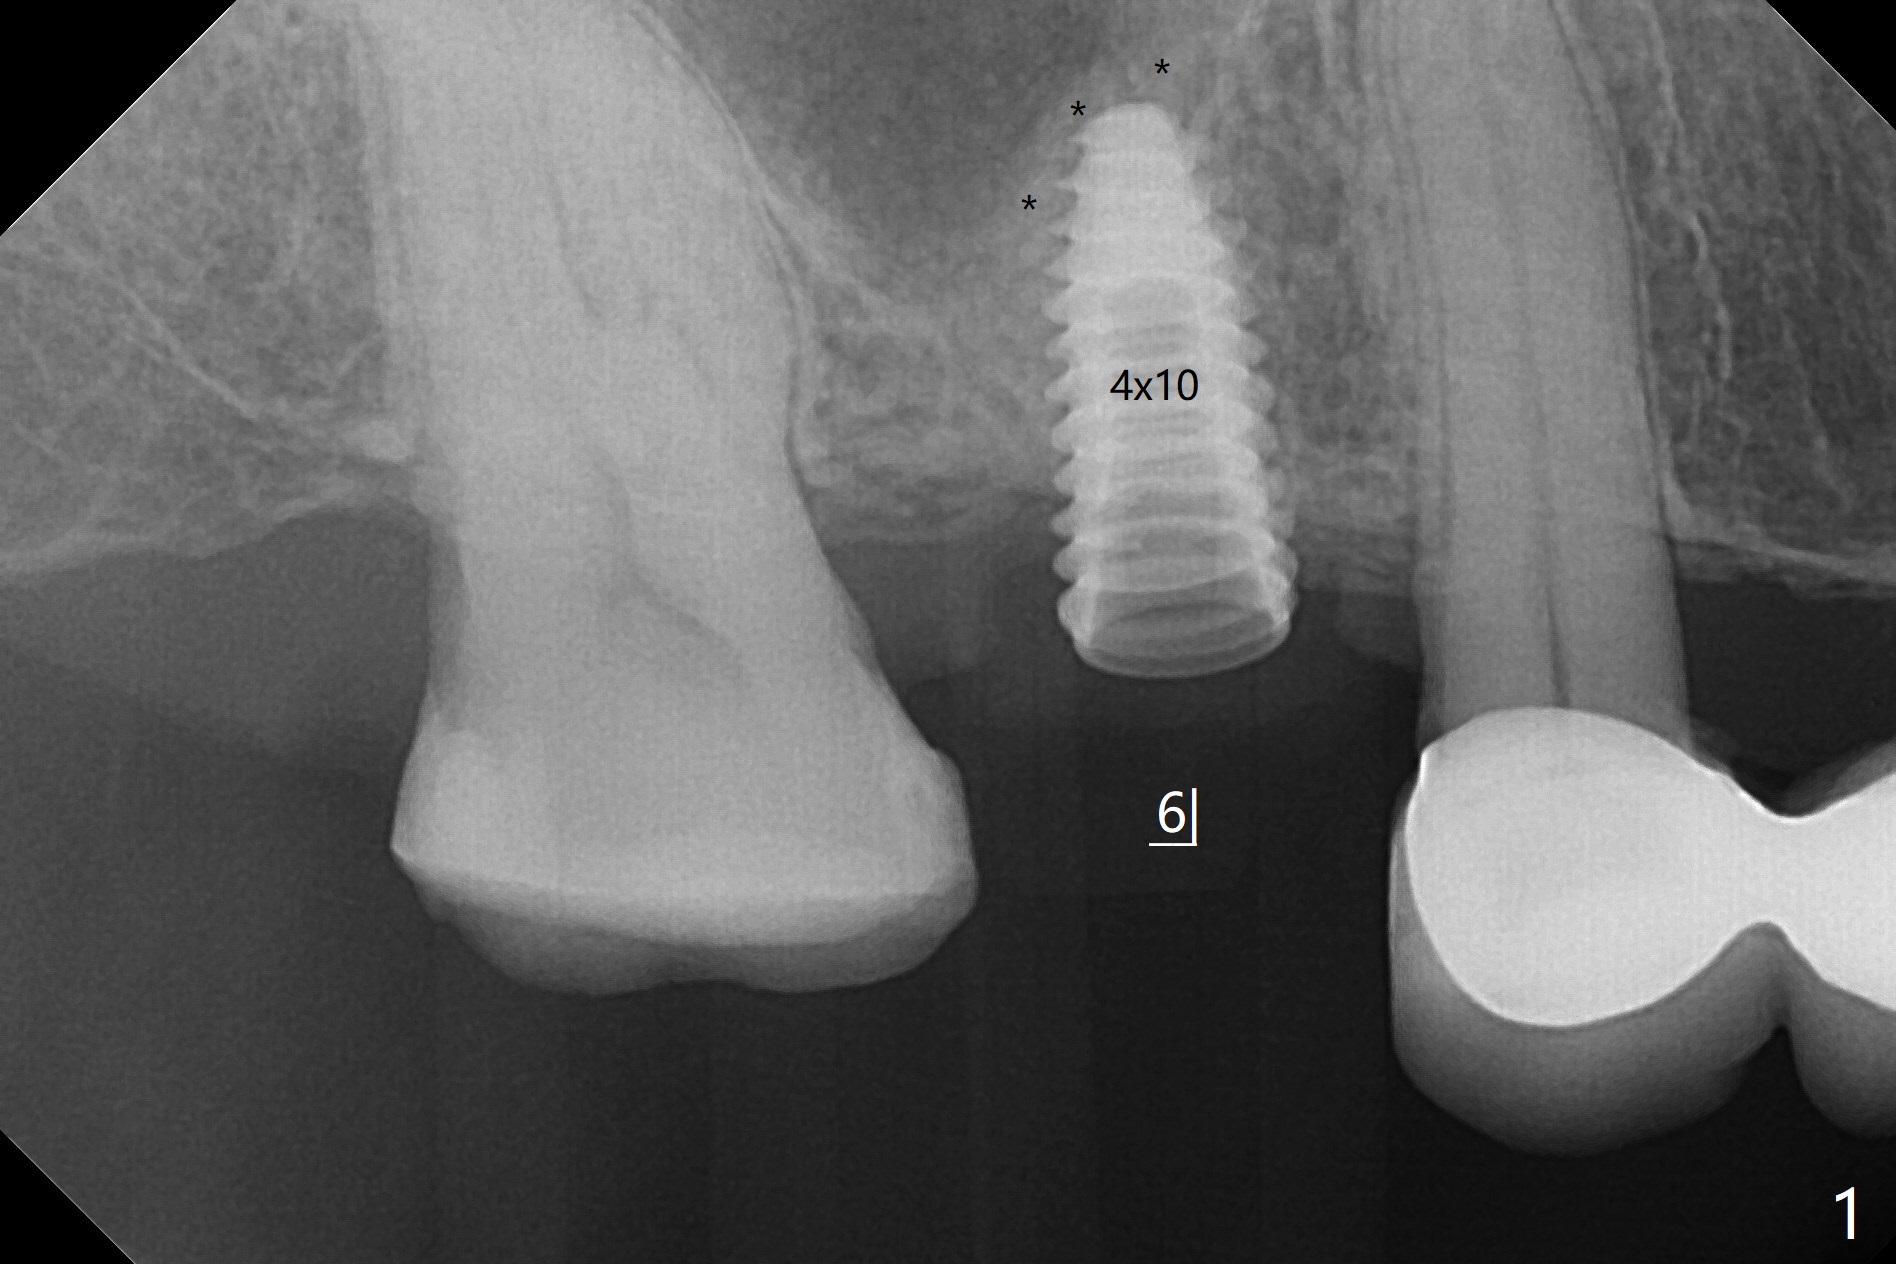

我们将使用粘性骨块做上颌窦内提升。抽血,一个红试管(含促凝剂),离心每分钟1500转,3分钟,提取上清液,与异体骨混合,几秒钟骨粉就开始凝聚(录像)。右上六缺牙区切开,开始用2毫米钻头钻洞,深度4毫米,如何使用2.8,3.6毫米园钻头(对上颌窦膜安全),4-6 毫米深,由于上颌窦底板是斜型,没有突破感。接着想利用粘性骨块和报废植体,把骨块送上去,这时骨块相当硬,必须事先剪成适当大小,然后用报废植体(4x10毫米)慢速推上去(录像2,图一(*骨块))。数次提升后,放置4.5x8.5毫米正式植体(图二),调整植体深度(图三:<),在稍微暴露植体表面放置骨块(图四:*)。其实愈合基台没有就位(图五:>),更换后没这个问题(图六)。